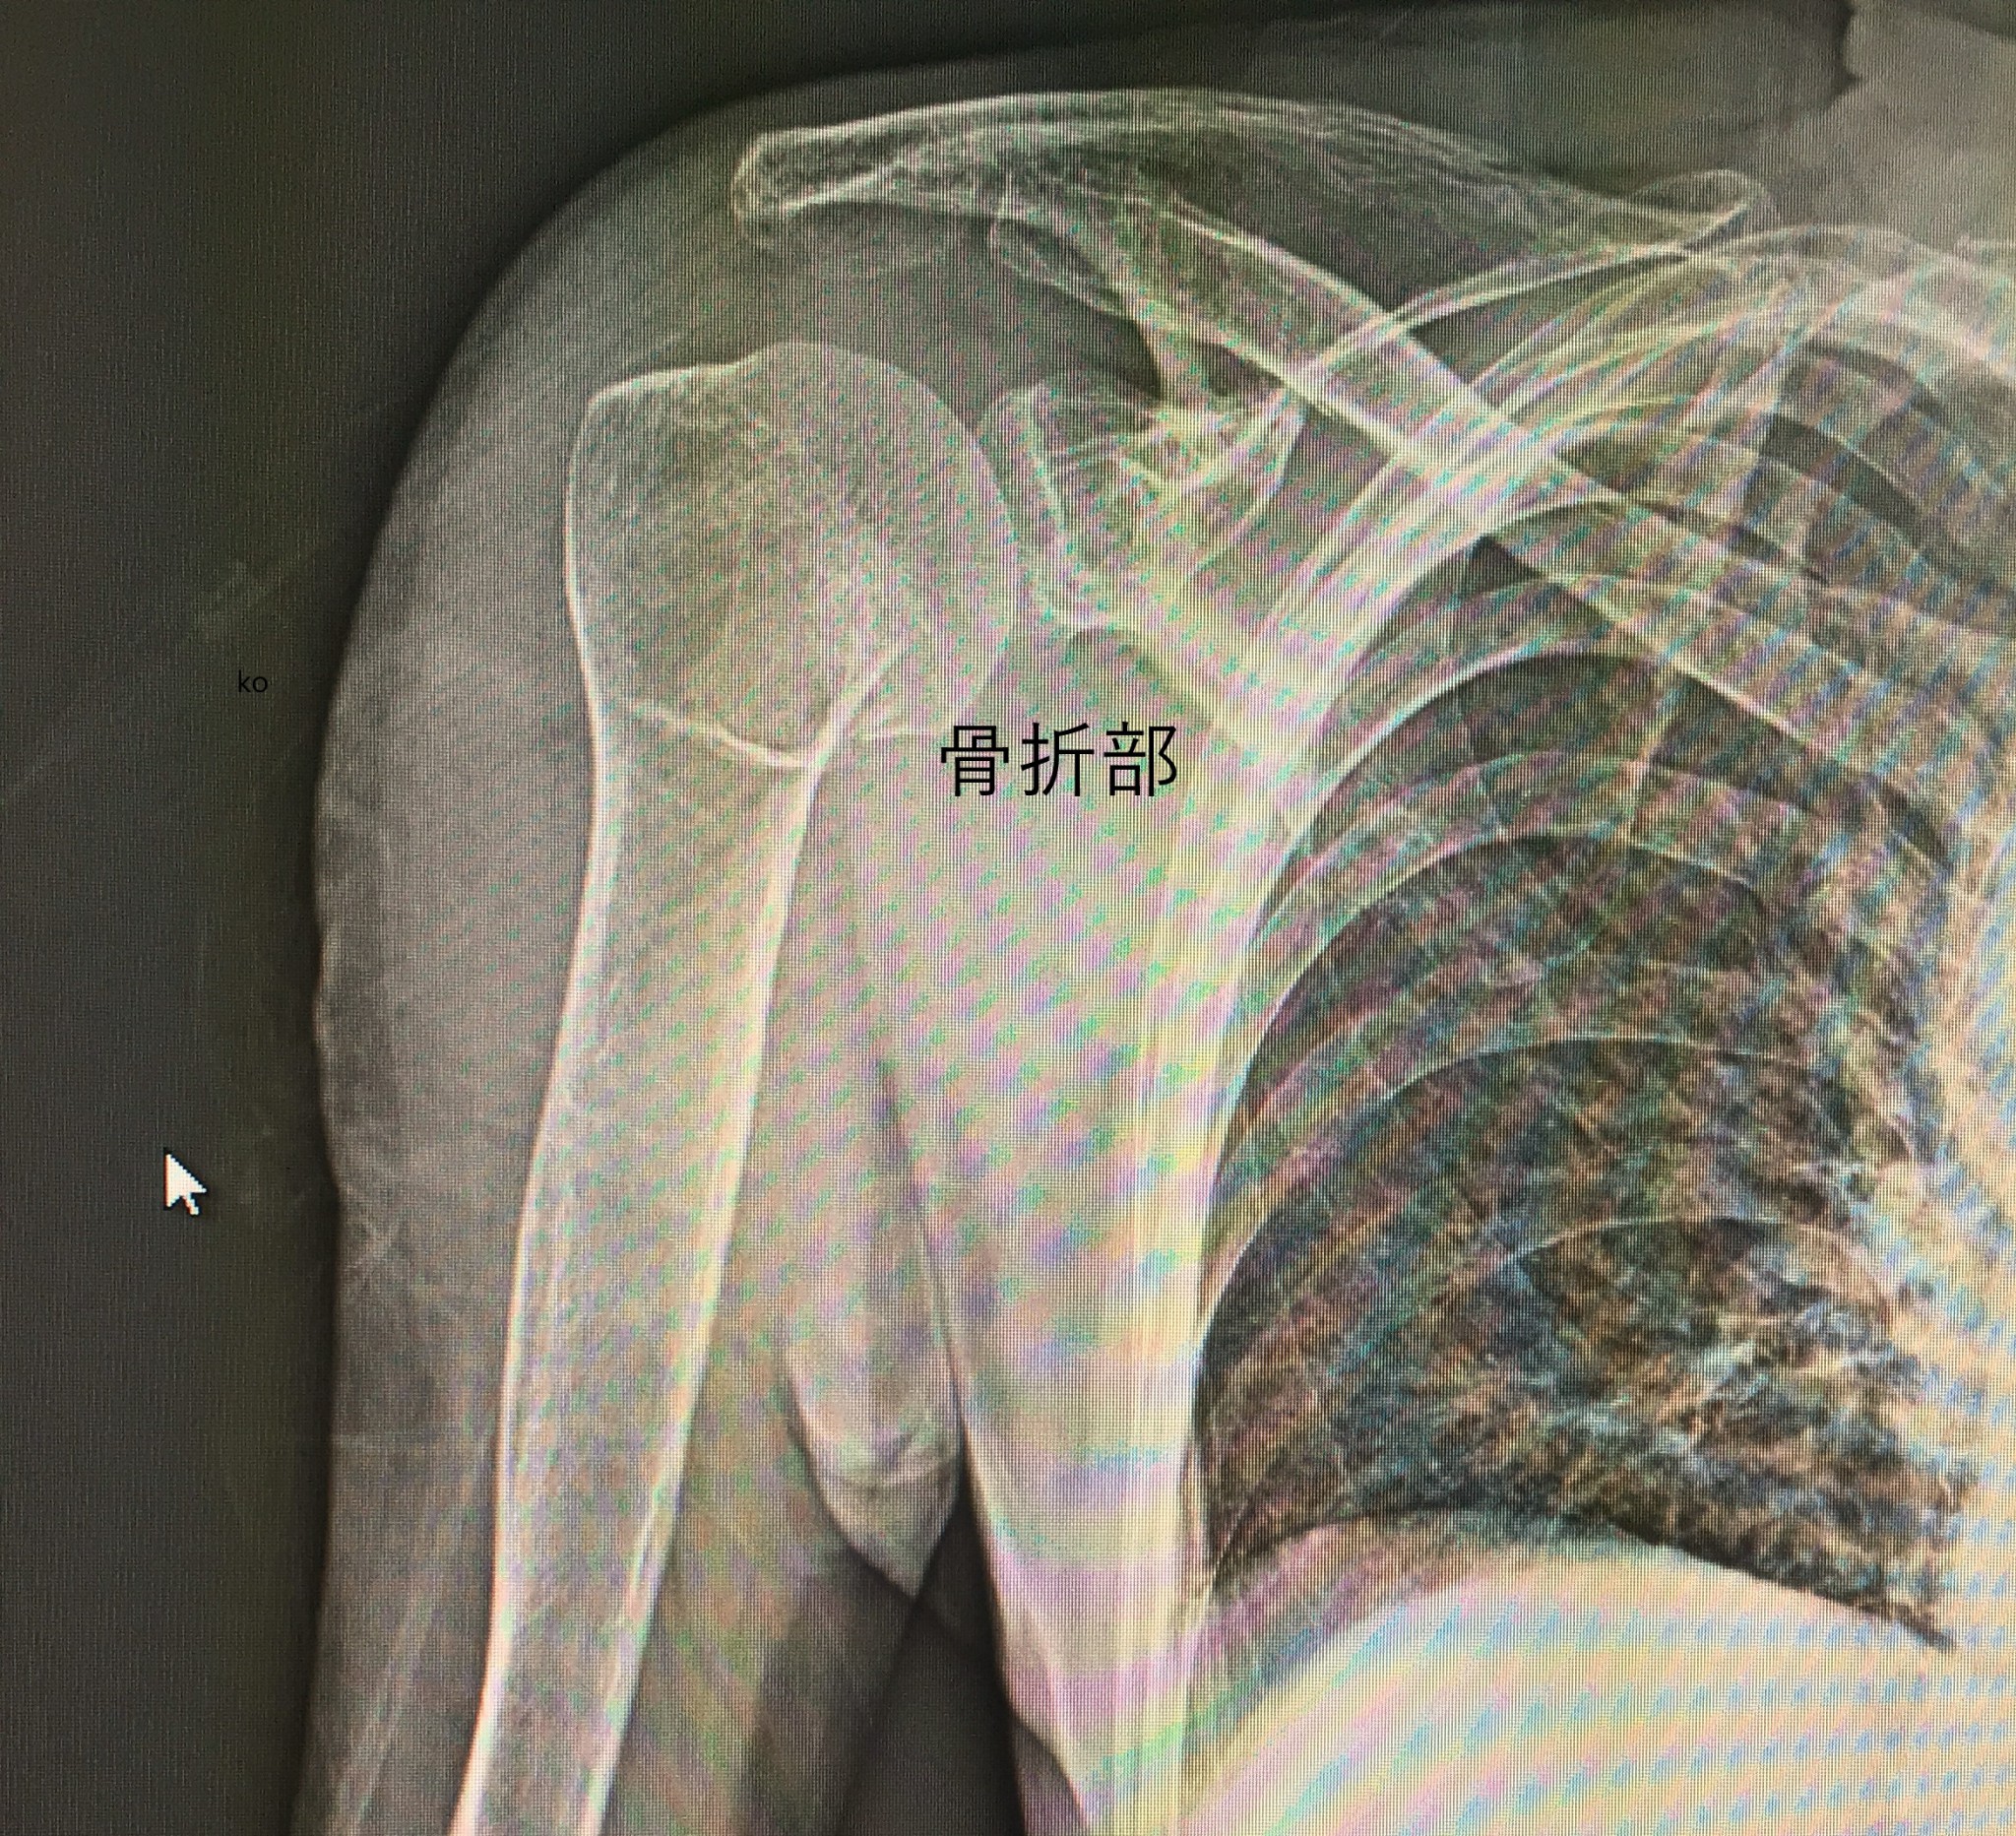

骨折の応急処置を専門に行っています。 上腕骨上端部骨折 上腕骨の上端部の骨折には、結節上骨折と結節下骨折があります。 介達外力によって発生し、少年期と老人に多いです。 直達外力の場合は、青壮年にもあります。 種類 ①結節上骨折  骨頭骨折、解剖頸骨折 ②結節下骨折  結節部貫通骨折、外科頸骨折、骨端線離開、大結節単独骨折、小結節単独骨折 1,上腕骨骨頭骨折 上腕骨骨頭骨折の単純骨折はまれです。 (原因) 1)介達外力による場合:上腕骨の上1/3の骨折において骨折線が骨端部の骨折に止まらず骨頭まで氷裂骨折の亀裂を起こします。 2)直達外力による場合:激突や重量物の落下などによる直達外力によって亀裂骨折をおこします。 (症状) 1)肩関節部における関節の挫傷、強大な打撲傷の様子を呈する 関節捻挫と誤診されやすいです。 2)関節内血腫をおこします 3)出血と痛みが甚大 4)腫脹は著しいが、結節部や外科頸骨折の腫脹に比べると少ない。 5)関節可動時の痛みが増大 6)関節窩に向かって圧迫し、かつ回旋すると轢音を聞くことがあります。 7)腕を挙上して腋窩にて骨頭を触知することによって骨折部を触診できることもある (整復・固定) 転位があるもの:観血療法 転位がないもの:外転位70~80°で固定 (後療法) 初期においては冷湿布を行う 骨性癒合まで関節運動を中止する 癒合期に機能訓練をする (予後) 骨性癒合が起こりにくいので、骨頭片は栄養障害により二次的壊死に陥りやすい 当院では、骨折の応急処置を行い、痛みを軽減した後に提携クリニックをご紹介しています。 痛みが強い時には、応急処置をしてから病院受診を勧めています。 骨折応急処置緊急ダイヤル:0800-200-3830